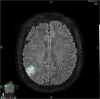

With the recent publication of a new World Health Organization brain tumour classification that reflects increased understanding of glioma tumour genetics, there is a need for radiologists to understand the changes and their implications for patient management. There has also been an increasing trend for adopting earlier, more aggressive surgical approaches to low-grade glioma (LGG) treatment. We will summarize these changes, give some context to the increased role of tumour genetics and discuss the associated implications of their adoption for radiologists. We will discuss the earlier and more radical surgical resection of LGG and what it means for patients undergoing imaging.